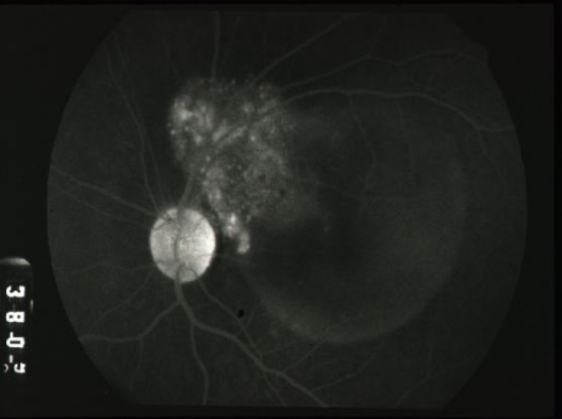

mottled fluorescence in arteriovenous phase, progressive staining, prolonged dye retention, double circulation

what does a choroidal melanoma show on IVFA?

choroidal melanoma

melanoma

melanoma

melanoma

melanoma

melanoma

melanoma

melanoma

melanoma

melanoma

melanoma

melanoma

melanoma

melanoma

melanoma

melanoma

melanoma